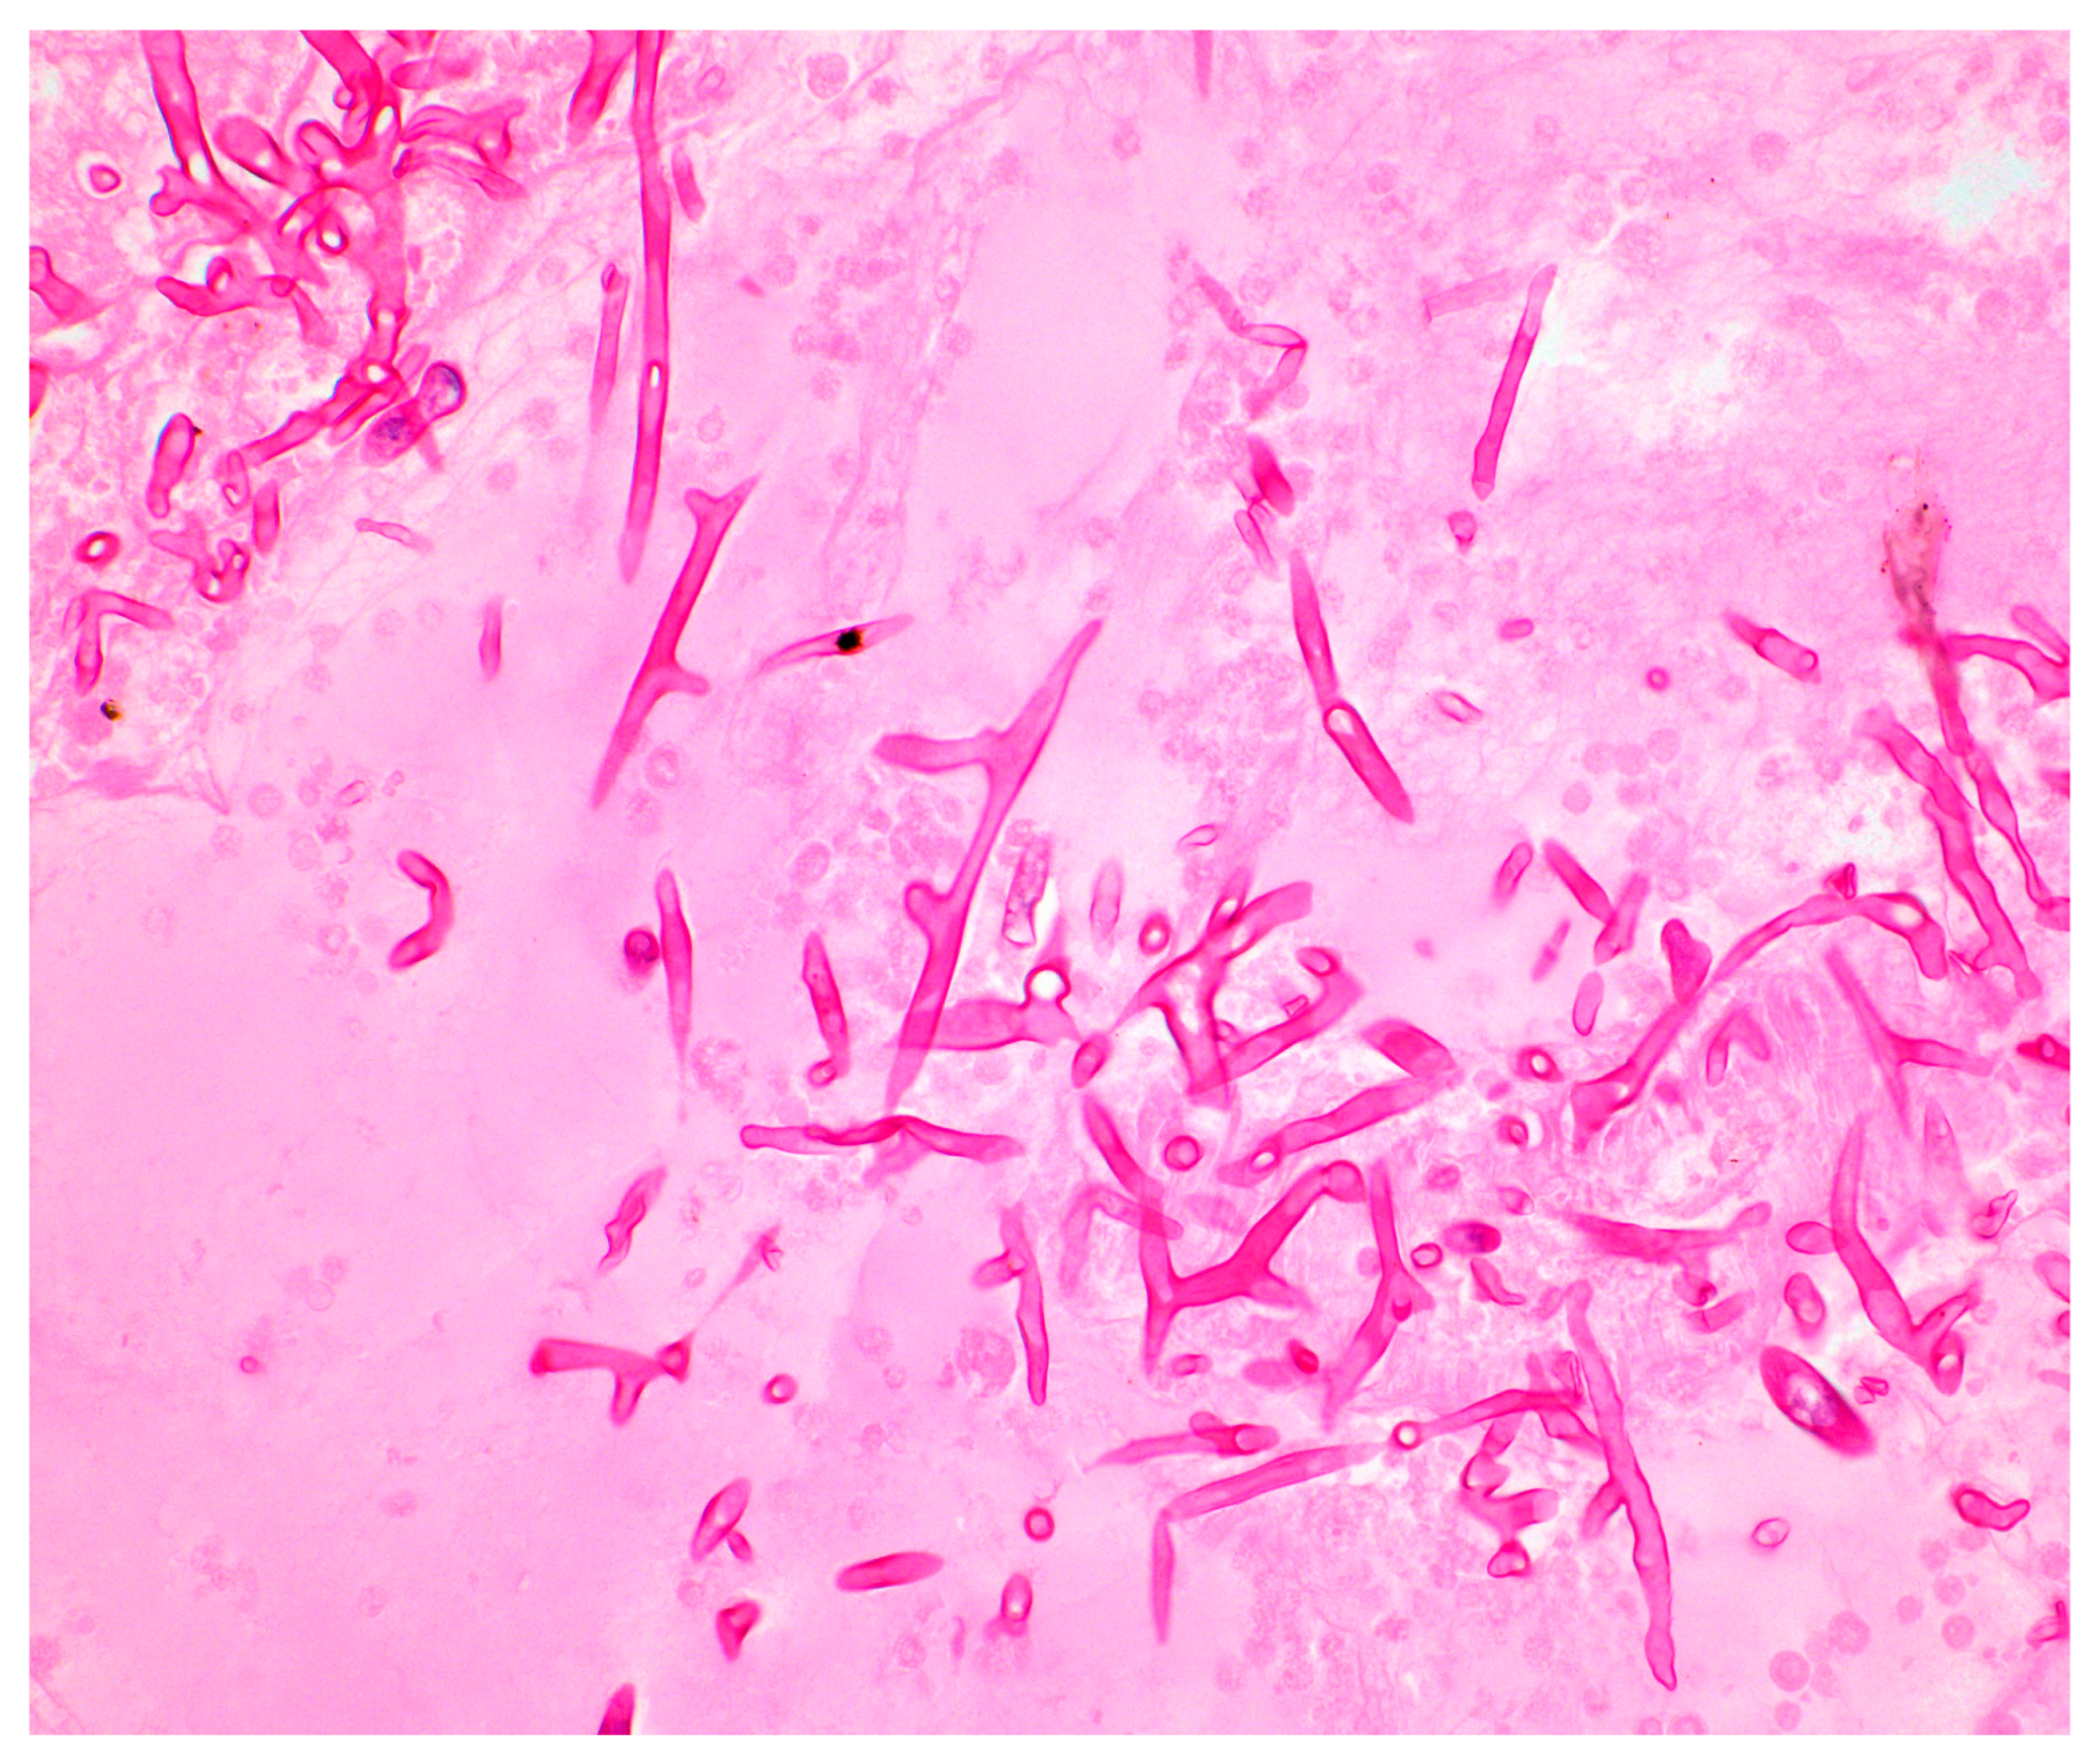

3.1. Direct Microscopy of Clinical Specimens

3.2. Histopathology